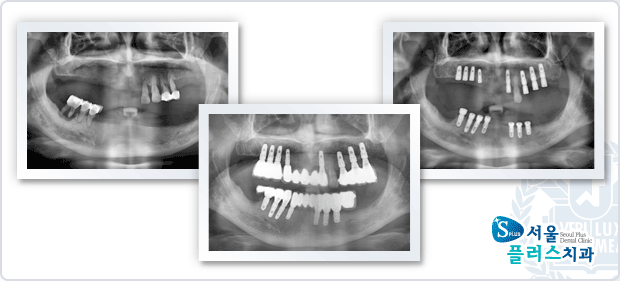

[임플란트] 임플란트 - 치주염으로 전악 발치 후 전악 임플란트 식립